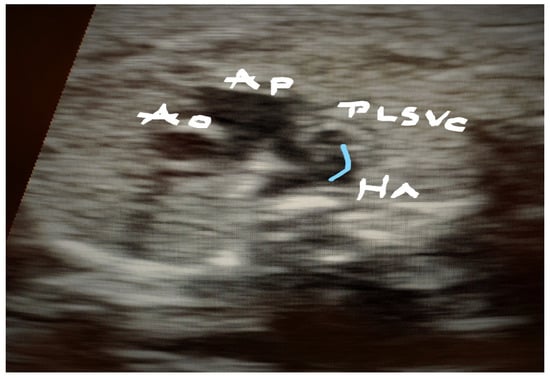

4.3. Case 3